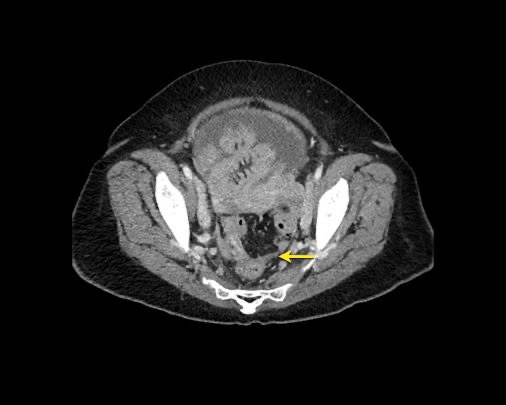

Ở vùng chậu, vị trí quan trọng nhất là túi cùng trực tràng-tử cung và trực tràng-bàng quang (túi cùng Douglas).

Đặc biệt khi bàng quang đầy, các tổn thương di căn phúc mạc có thể được quan sát thấy ở phía trước bàng quang, áp sát thành bụng trước.

Đây không phải là bệnh lý quanh bàng quang, vì khoang quanh bàng quang nằm ngoài phúc mạc và không thông với khoang trong phúc mạc.